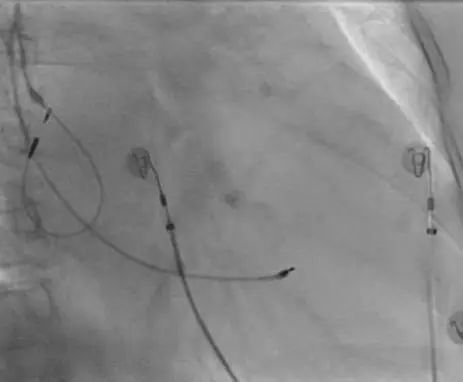

术中HIS电极影像

LBB影像位置

术中影像 HIS-HISD-消融靶点